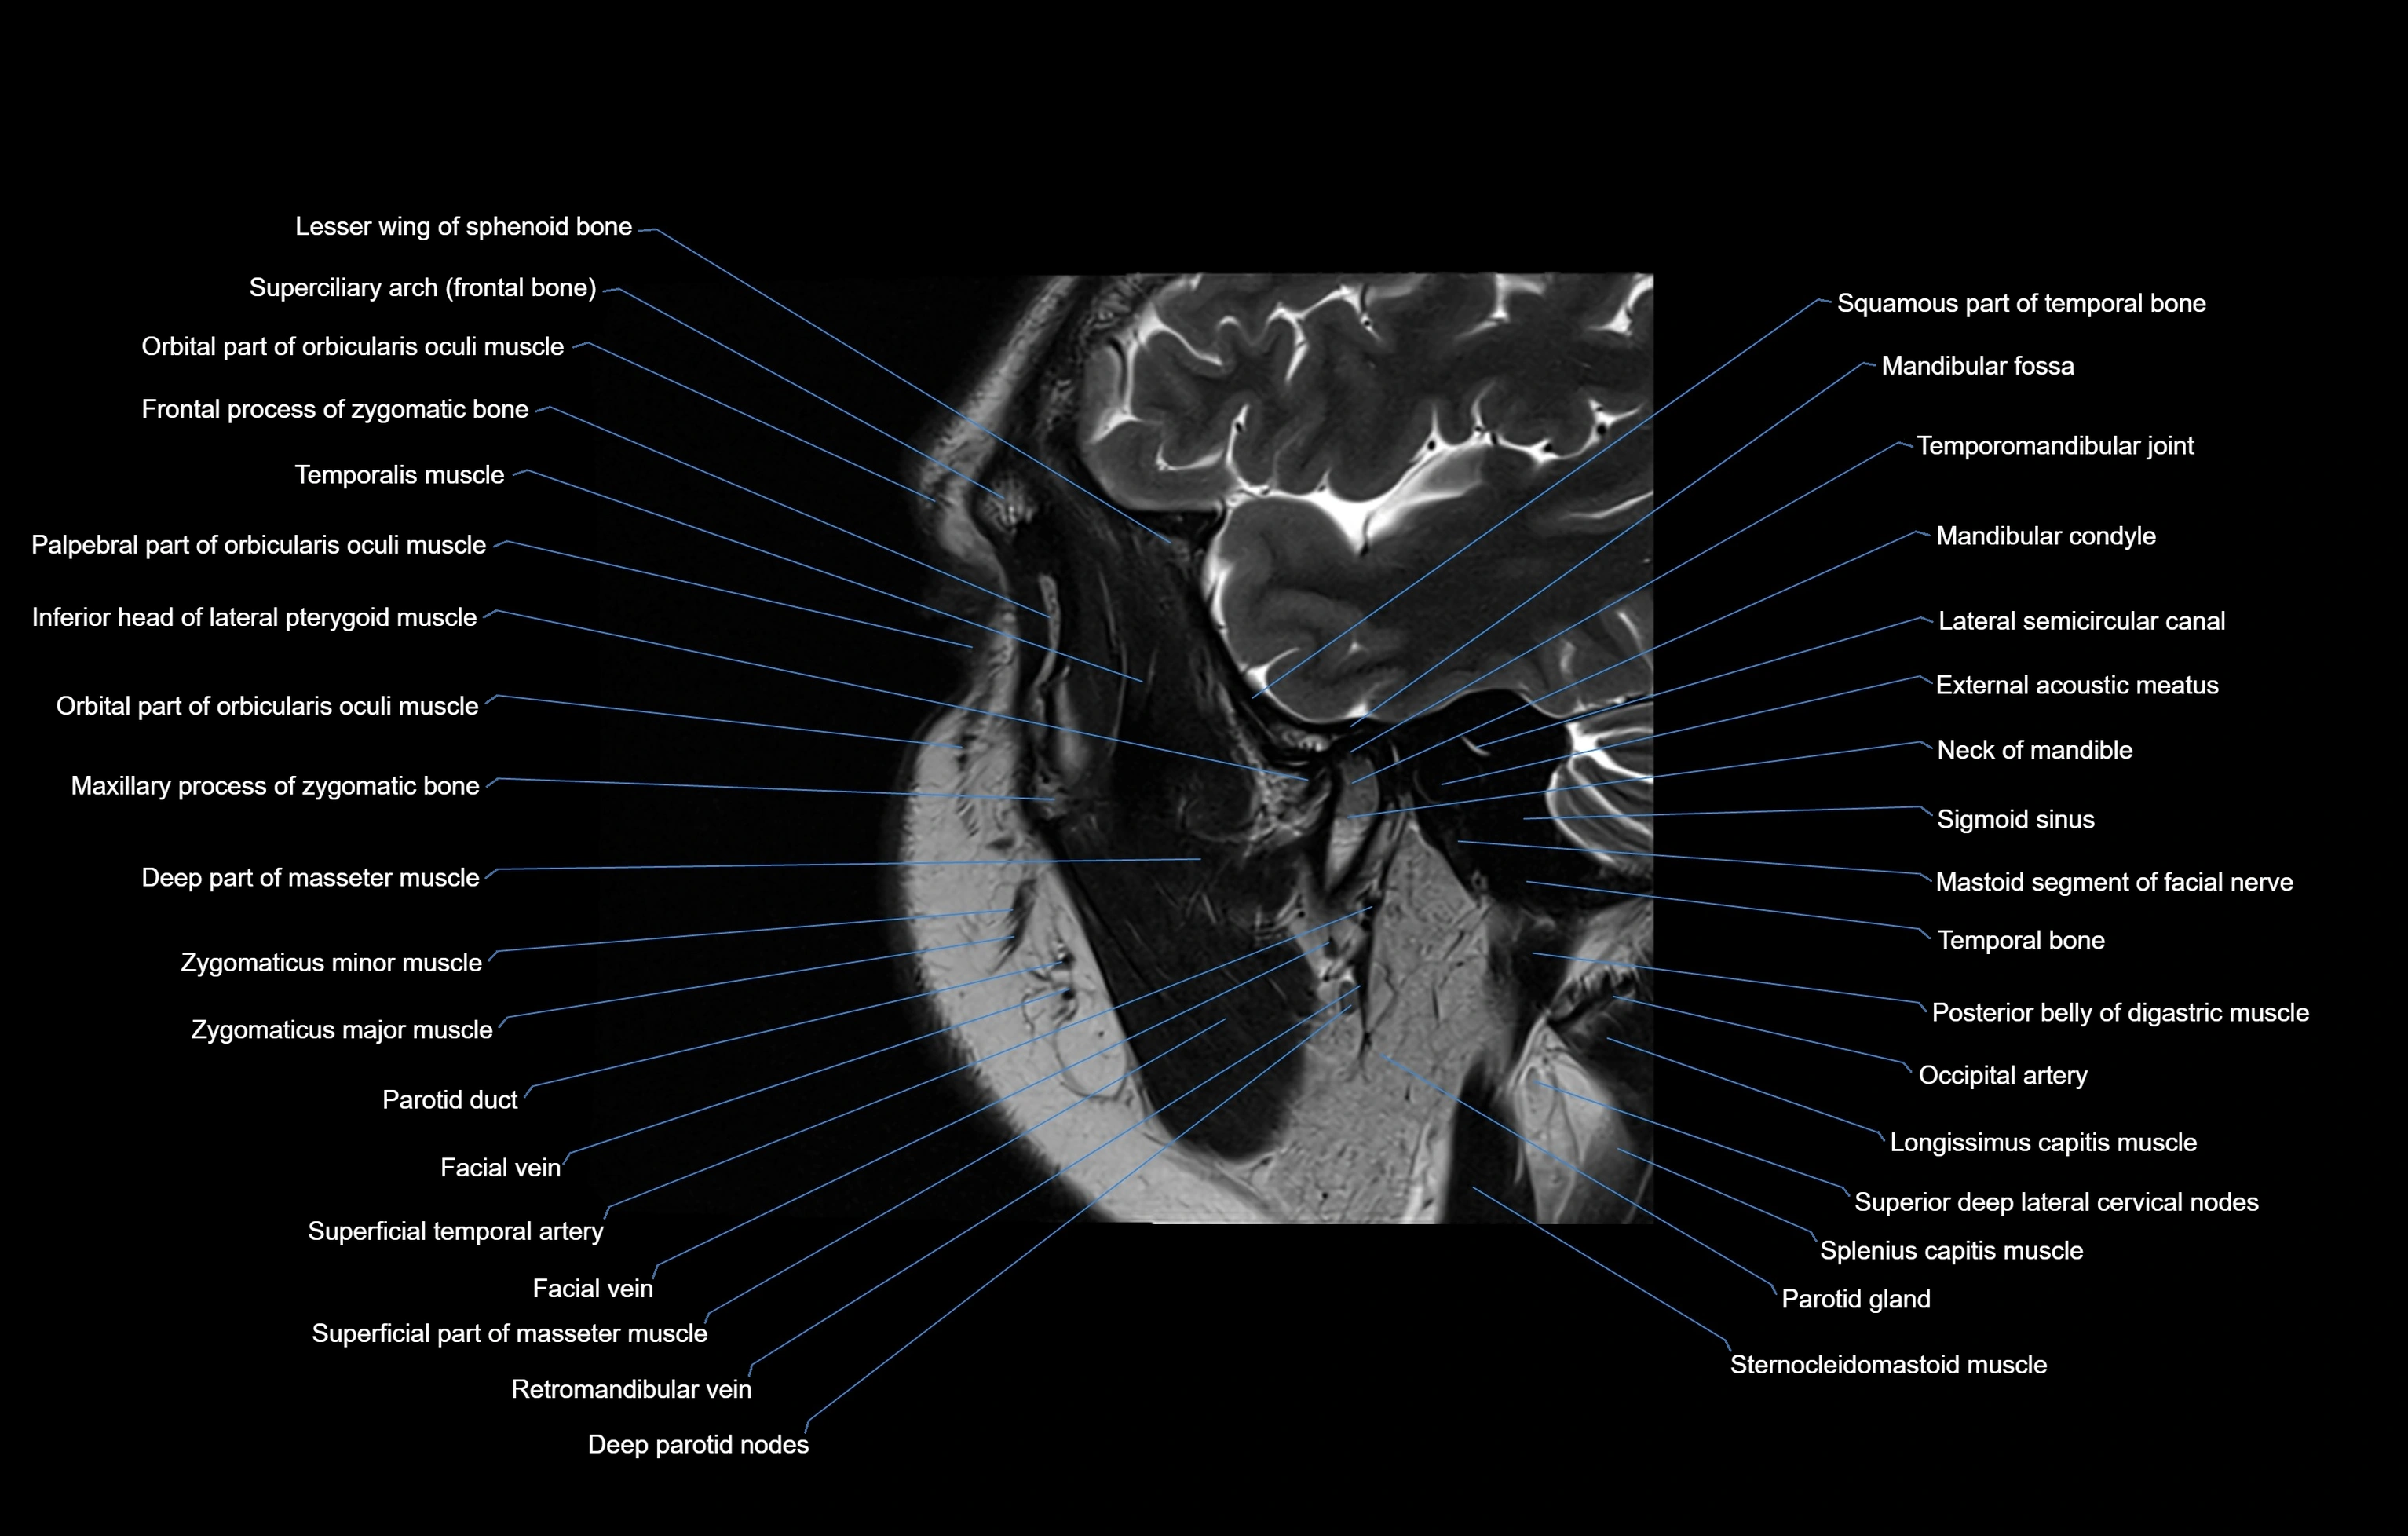

MRI images